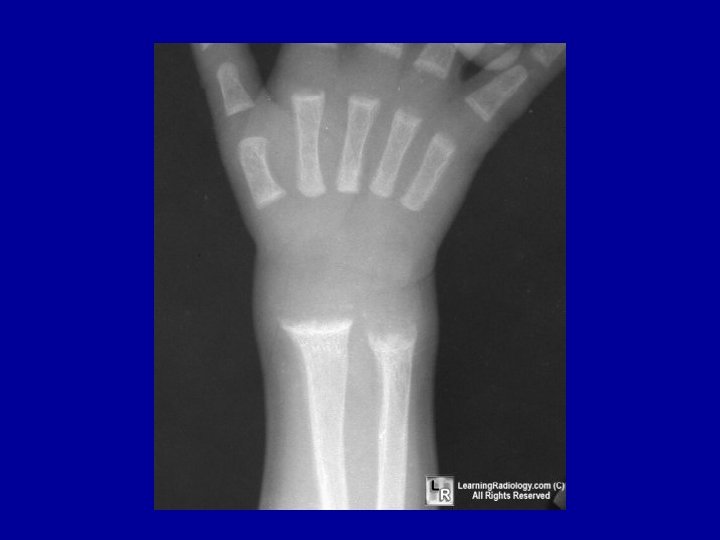

Radiological changes These are best seen at the lower end of the radius and ulna A-Active rickets 1 -Distal ends are widened, cupped or concave and frayed and ill defined 2 -Wrist joint space ---is wide 3 -Rarefaction--- decrease bone density 4 - Green stick fracture and deformities

Classic radiographic findings include Anteroposterior and lateral radiographs of the wrist of an 8 -yearold boy with rickets demonstrates cupping and fraying of the metaphyseal region

Radiographic image of wrist and forearm showing pathologic fractures of radius and ulna with rachitic changes of distal end of radius and ulna.